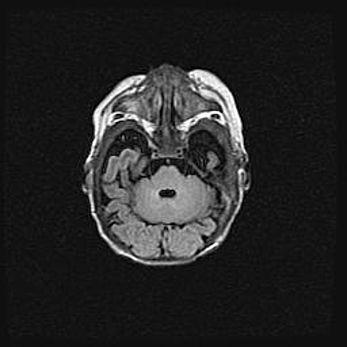

Церебральная ишемия II.

Возраст: 5 дней

Вес: 3400 г

Пол: женский

Окружность головы: 35 см

Срок гестации: 39 недель

Церебральная ишемия – это заболевание, характеризующееся недостаточностью (гипоксией) либо полным прекращением (аноксией) снабжения мозга кислородом по причине закупорки одного или нескольких сосудов. Это приводит к  что метаболическим расстройствам различной степени тяжести в тканях головного мозга, развитию коагуляционных некрозов и гибели нейронов.